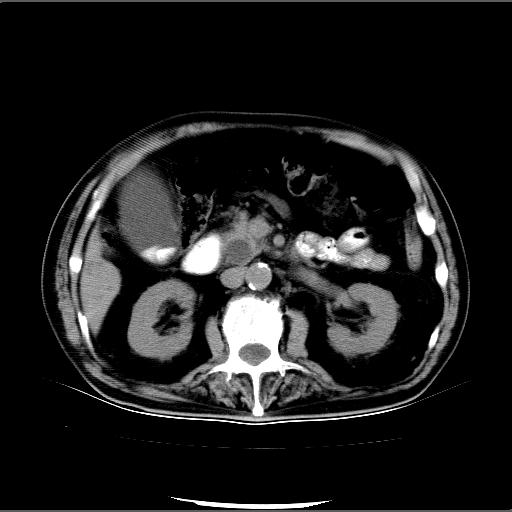

患者男82岁,黄染,发热10天,无腹痛。

1胆总管下端结石伴肝内外胆管扩张;2胆囊颈部结石伴胆囊积液

胆囊多发结石,胆囊积液;胆总管中下段结石,中上段扩张。

胆总管下段结石伴胆道系统扩张;胆囊炎伴胆囊结石.

有时胆总管下段结石的密度并不是均匀的高密度,而是以高密度为主的伴中心等密度的混合物,这与胆道结石的多样性有关,少数时候诊断困难时应结合临床病史,症状等,还有增强扫描都可以帮助明确诊断!!常与胆道蛔虫伴钙化鉴别!

十二指肠乳头旁憩室伴胆总管下段结石,胆囊结石

此病例有结果了:患者术后为:胆总管下段结石伴胆道系统扩张;胆囊炎伴胆囊结石。

各位战友分析的都很正确,是一个典型的病例。